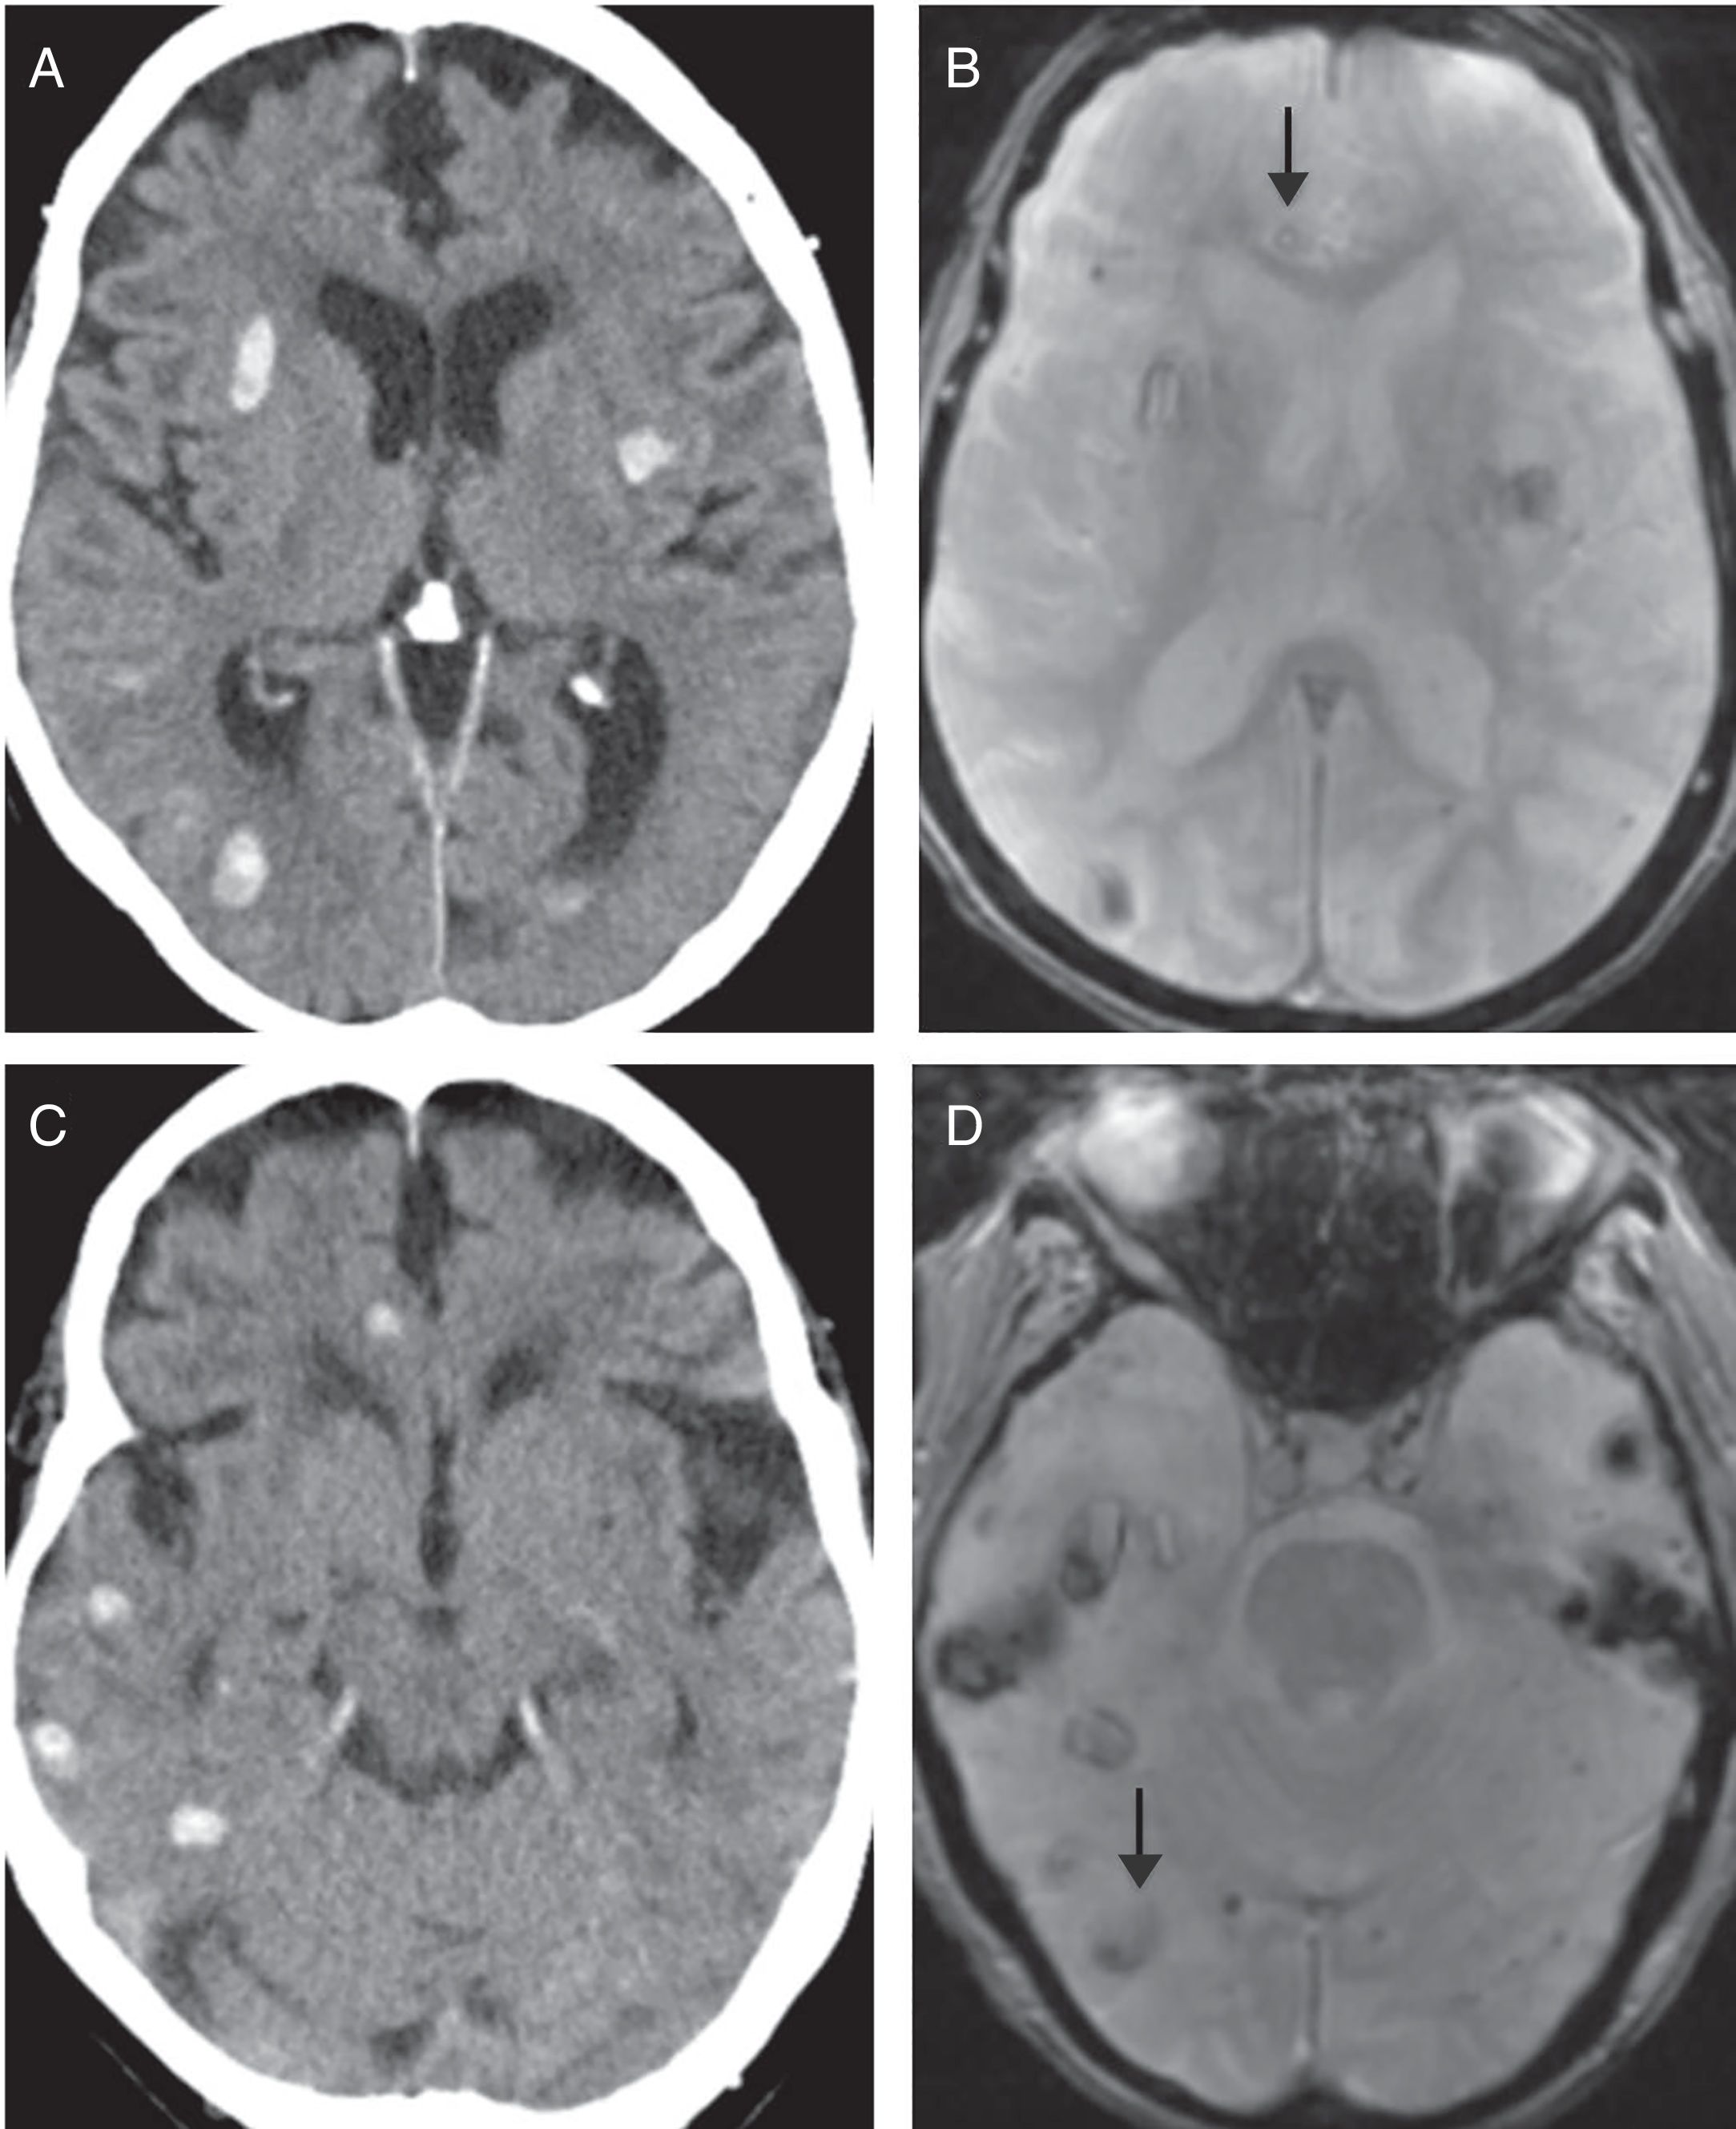

Presentamos el caso de una mujer de 90 años con antecedentes de accidente isquémico transitorio carotídeo izquierdo y estenosis aórtica leve. Acudió a urgencias con afasia motora de inicio desconocido. En la exploración física se obtuvo un NIHSS 5. Se activó el Código Ictus y se realizaron tomografía computarizada (TC) cerebral, TC de perfusión cerebral y angio-TC de troncos supraaórticos-polígono de Willis, que pusieron de manifiesto un estudio basal con ASPECTS 10, un área de penumbra isquémica en el territorio de la arteria cerebral media izquierda y un trombo en el segmento M2 distal ipsilateral (fig. 1 A-E). A pesar de la edad avanzada de la paciente, dada la buena calidad de vida previa y los hallazgos de las pruebas de imagen, se inició terapia fibrinolítica. Pasadas 24 horas postratamiento, la paciente mostró mayor deterioro neurológico. Se solicitó una TC cerebral de control donde se visualizaron múltiples focos de sangrado intraparenquimatosos lobares y difusos (fig. 1 F-H). La distribución de los focos hemorrágicos, alejados del territorio afectado por el área de penumbra, descartó una transformación hemorrágica. Ante la sospecha de angiopatía amiloide (AA) se solicitó una resonancia magnética (RM) cerebral como prueba complementaria. Con base en los criterios de Boston, la RM apoyó el diagnóstico de “probable” AA, al demostrar múltiples focos de sangrados antiguos visibles en la secuencia eco de gradiente T2 (fig. 2). Al alta, la paciente mantenía un cuadro de disfasia mixta.

Estudio comparativo de resonancia magnética (RM) cerebral secuencia eco de gradiente con tomografía computarizada (TC) cerebral sin contraste intravenoso. Debido a la diferente programación y el distinto grosor de corte empleados en los estudios de TC y RM, utilizando la línea orbitomeatal en la TC y la subcallosa en RM, las imágenes obtenidas no coinciden al 100% en su situación. Para orientarnos en la valoración comparativa, tomamos como referencia las astas ventriculares frontales en A, B y la fosa posterior en C y D. Las flechas señalan focos de hemorragia antiguos visibles en RM secuencia de gradiente, pero no en la TC. Estos hallazgos apoyan el diagnóstico de angiopatía amiloide según los criterios de Boston.

La AA se debe al acúmulo de la proteína β amiloide en pequeños y medianos vasos, lo que condiciona mayor fragilidad vascular. El envejecimiento constituye el principal factor de riesgo, y es más frecuente en personas de edad avanzada4, las cuales presentan mayor incidencia de patología isquémica cerebral. La principal manifestación radiológica de esta entidad (AA) considerada en los criterios de Boston es la presencia de hemorragias agudas/crónicas de distribución cortical y/o corticosubcortical4. El diagnóstico diferencial debe plantearse con otras patologías que pueden causar sangrado cerebral, como hipertensión arterial, malformaciones cavernomatosas múltiples y traumatismos cerebrales previos. Por tanto, debe realizarse un diagnóstico de exclusión, y es importante tener presente que la característica distribución con respeto de los núcleos grises profundos y el tronco del encéfalo permite distinguirla de la hemorragia secundaria a la hipertensión arterial4.

Como ya se ha comentado, estudios realizados han planteado que existe una posible asociación entre angiopatía amiloide y HICr postratamiento2,3. Los focos de microsangrado, visibles en RM pueden actuar como marcadores de AA concomitante. Basándose en esto, la inclusión de una RM cerebral pretratamiento permitiría predecir el riesgo de sangrado postratamiento5, lo que facilitaría la selección de aquellos candidatos a tratamiento fibrinolítico. No obstante, aún no existen evidencias suficientes para probar este hecho y justificar la contraindicación de tratamiento de una patología grave y prevalente como es el ictus isquémico3.